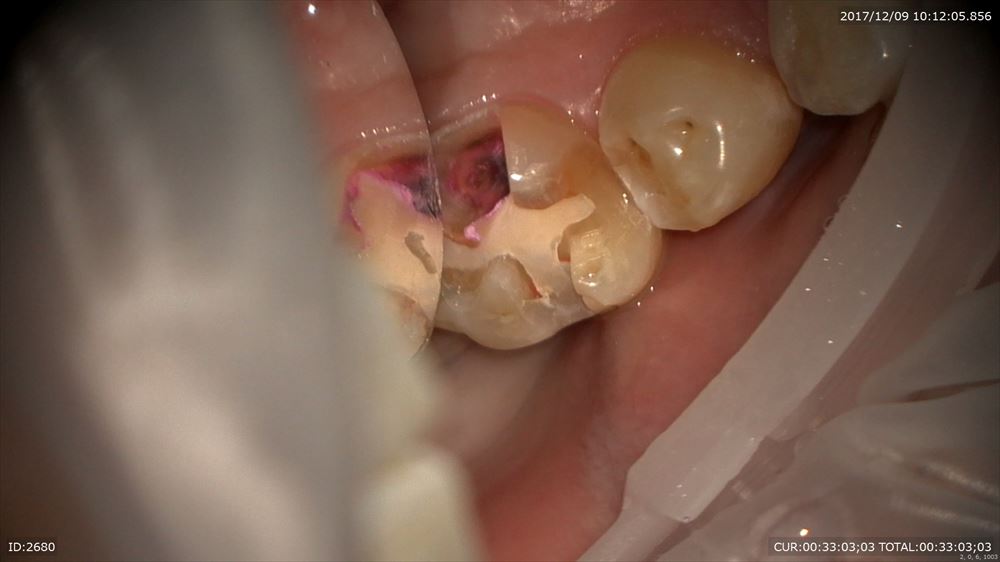

精密根管治療の難しい所は根管内だけではありません。この方は右上7番一番アプローチしずらい所。

難しいのはいかに上部形成を行うか。エンドの基本。その為の準備

まず被せ物を外し

ここからコアを除去。金属が口に入ったり口を絶対に傷つけないためのラバーダム(必須!!)金属を飲んだら大変です。ラバーダムをしないで根管治療を行う事は当院では100%ありません。

やはりこんなに感染が

上部形成。ストレートラインアクセス

ガッタパーチャを除去D3使用

ん?

もう1根MB2あった。これが病変の原因か。

レーザー

これで90分の1回目のメニューは終了。